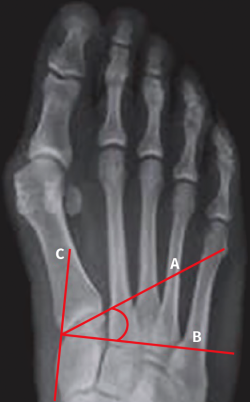

En una radiografía dorsoplantar en carga se mide el ángulo formado por una línea (A) que se traza al nivel de la base del primer metatarsiano y la línea perpendicular (B) al eje mayor del primer cuneiforme sobre la cortical interna del mismo (C). Su valor normal es de 0 a 8°, aunque puede encontrarse una gran variabilidad en relación con la incidencia radiológica utilizada(47)(Figura 8).

Figura 8. Medición del ángulo de inclinación de la primera articulación tarsometatarsiana. Se obtiene en una radiografía dorsoplantar en carga. Se mide el ángulo formado por una línea que se traza al nivel de la base del primer metatarsiano (A) y la línea perpendicular (B) al eje mayor del primer cuneiforme en la cortical interna del mismo (C).

En un trabajo reciente(48), evaluamos la relación existente entre el grado de inclinación de la 1.ª ATMT y el valor angular entre el metatarsiano primero y el segundo. Por lo general, cuando la oblicuidad de la articulación es importante, el valor angular está aumentado. Sin embargo, no hemos encontrado una relación directamente proporcional entre el aumento del AIMT y la inclinación de la 1.ª ATMT.